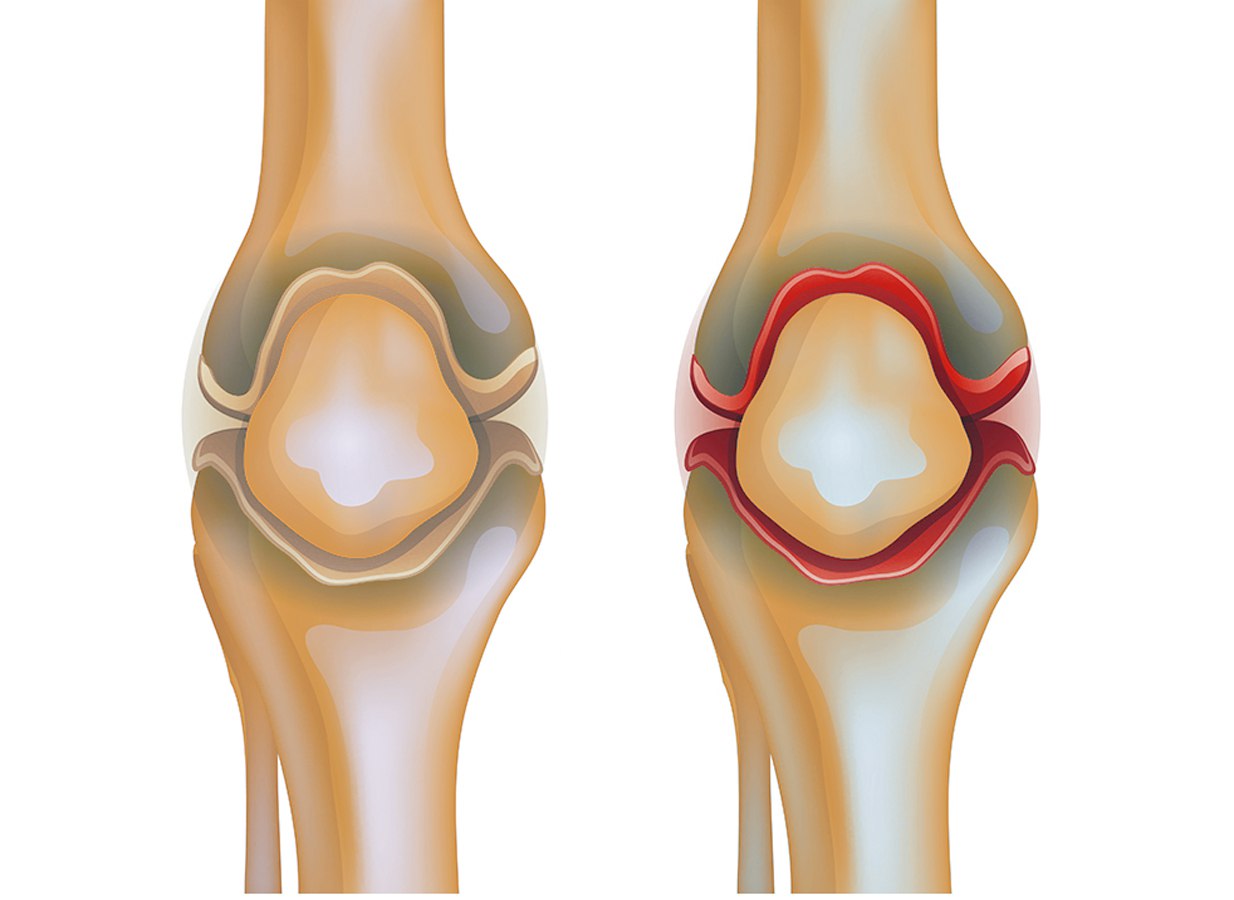

Медицинские состояния: Септический артрит коленного сустава